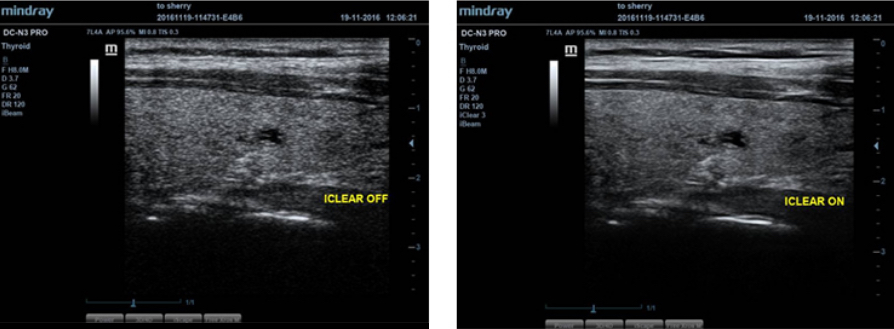

iClear?

Otomatik yap? denetimine dayal? geli?mi? g?r├╝nt├╝ kalitesi kazan?m?

- Daha Belirgin ve S├╝rekli Kenarlar.

- Yumu?ak Tek Tip Dokular.

- Daha temiz "ekosuz alanlar".